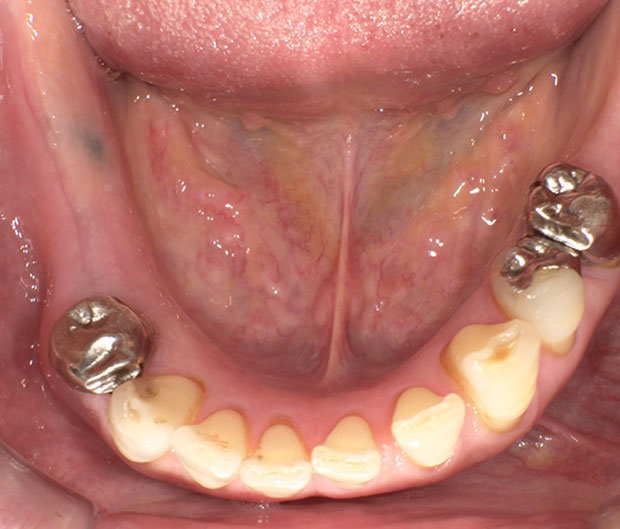

周りの歯を多少削って型取り、次回完成となります。周りの歯にバネをかけて引っかけます。ご自身で着脱してもらう物になります。

入れ歯を一言で表現するなら『保険で出来るけど固い物は食べれない』(個人差あり)です。入れ歯は個人差はありますが、固い物が食べれなくなる物だと思っておくのが無難です。例えば、右側に入れ歯をいれた人に話を聞くとほぼ左で食事してる、と大概は言われます。

上の患者さんに渡す紙にも記載ありますが、咬む力は自分の歯の20%程度になると言われてます。あと、バネがありますしそれなりの大きさなので、異物感を訴える方がほとんどです。中には気持ち悪くてつけてられないなんて方もいらっしゃいます。さらには、ご自身で着脱をして頂くので、食事後は磨いてもらったり、義歯用洗浄剤につけて頂いたりして管理しなければいけません。

左右を連結する針金に違和感を強く訴える方が多いです。